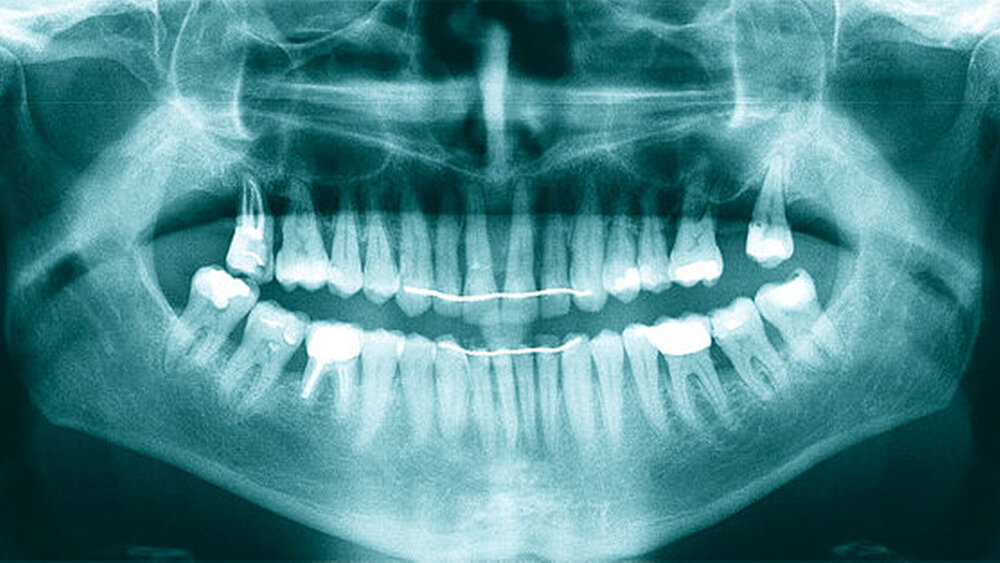

Röntgenologisch stellte sich im Orthopantomogramm der bereits intraoral ersichtliche horizontale und vertikale Knochenabbau mit Attachmentverlust an einzelnen Zähnen dar. Die Erhaltungswürdigkeit einzelner Zähne war aufgrund des starken Knochenverlustes beziehungsweise der Beeinträchtigung des Halteapparates als kritisch zu beurteilen.

Zudem wurde die Diagnose einer Parodontitis gestellt, die eine Rücküberweisung an den Hauszahnarzt erforderlich machte (Abbildung 2).